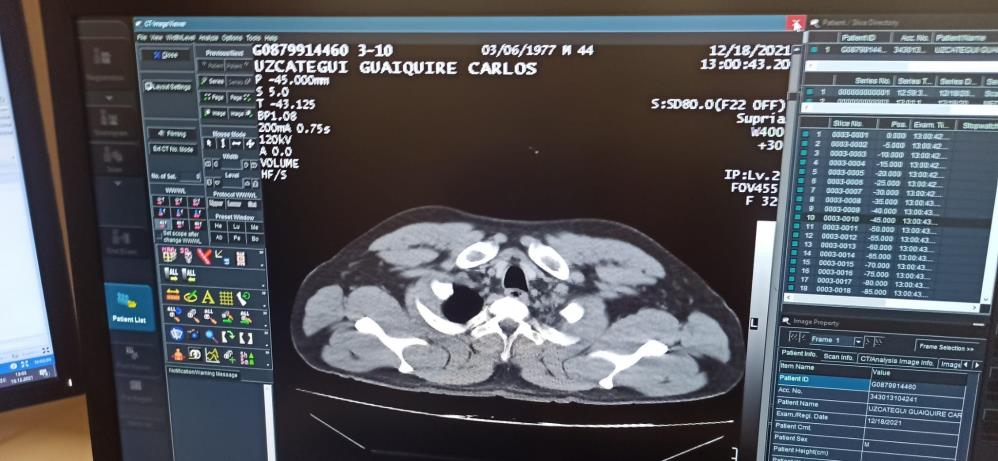

Yapılan ilk muayenenin ardından şahıs tedavisi için hastaneye kaldırıldı. C.M.U.G'un hastanede yapılan tomografi kontrolünde mide ve bağırsaklarında 12 adet kapsül tespit kokain tespit edilmesini üzerine şahıs ameliyata alındı.